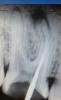

Денис481 Опубликовано 14 января, 2013 Поделиться Опубликовано 14 января, 2013 Пришла девушка болит зуб,зуб ранее лечен рф,прошел каналы,из них вышло много гноя,и плюс была перфорация,промыл,каласепт,отправил домой до пятницы,как думаете прогноз сего зуба Ссылка на комментарий

Денис481 Опубликовано 14 января, 2013 Автор Поделиться Опубликовано 14 января, 2013 Вот фото Ссылка на комментарий

Денис481 Опубликовано 14 января, 2013 Автор Поделиться Опубликовано 14 января, 2013 перфа была,там все устья найдены были,я только 2 канала прошел,а в мед щечный ручным полез он не идет,я думаю посмотрю направления каналов,поставил в те устья файлы а там такая картина Ссылка на комментарий

johniola Опубликовано 21 января, 2013 Поделиться Опубликовано 21 января, 2013 там корень резорбированный или мне так видется? Ссылка на комментарий